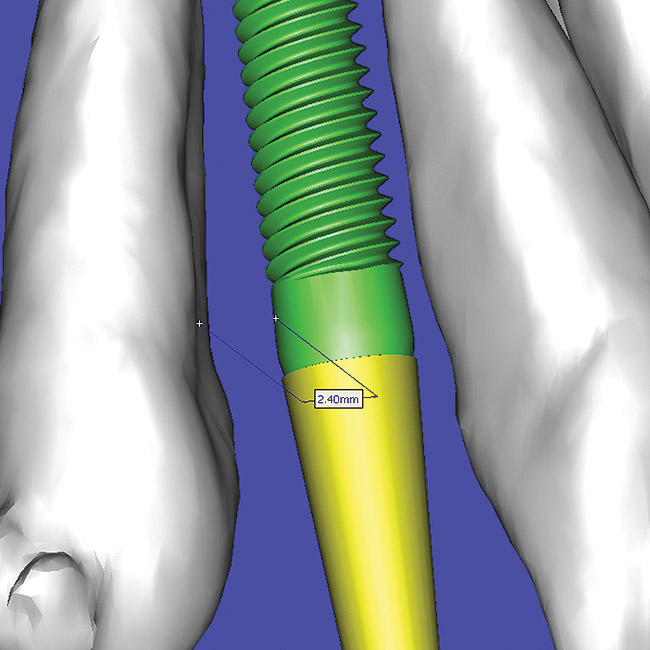

Using different masking (segmentation) and threshold Hounsfield unit values, several new 3D bone volumes can be created which offer invaluable information. To help determine the final position of each implant a new bone model was created with a Hounsfield unit value of 1480, which eliminated all but the densest objects included in the scan data. (Results may vary depending on the CBCT machine used.) The inner and outer layers of bone were removed, leaving the underlying enamel and root structure of the teeth (Figure 14). After the bone had been stripped away, the root inclinations were examined closely. The most striking findings confirmed the rotated position of the right central, while revealing the slight mesial dilaceration of the root apex, which converged on the space needed for the path of the potential implant (Figure 15). The schematic shapes of the proposed implants were visualized for the right and left lateral spaces in different rotations of the 3D maxillary arch. It was at this point that a determination was made as to the appropriate implant shape and type that would fit the available space while avoiding encroachment on adjacent tooth roots. A tapered design implant (Tapered Screw-Vent®, Zimmer Dental, www.zimmerdental.com) was chosen from the large virtual library. With the SIMPlant software, the virtual library contains data from dozens of implant manufacturers and realistic computer-aided design representations as seen in Figure 16 through the translucent bone. The position of the left implant can be visualized with adequate mesial-distal distance between adjacent tooth roots (Figure 17) and a more delicate placement (Figure 18).

Figure 16  SOFTWARE IMAGING Virtual implants were placed to determine the appropriate shape and type for the available space, in this case a tapered design allowed for adequate mesial-distal distance between adjacent roots.

Figure 16

Figure 17   SOFTWARE IMAGING Virtual implants were placed to determine the appropriate shape and type for the available space, in this case a tapered design allowed for adequate mesial-distal distance between adjacent roots.

Figure 17

Figure 18   SOFTWARE IMAGING Virtual implants were placed to determine the appropriate shape and type for the available space, in this case a tapered design allowed for adequate mesial-distal distance between adjacent roots.

Figure 18